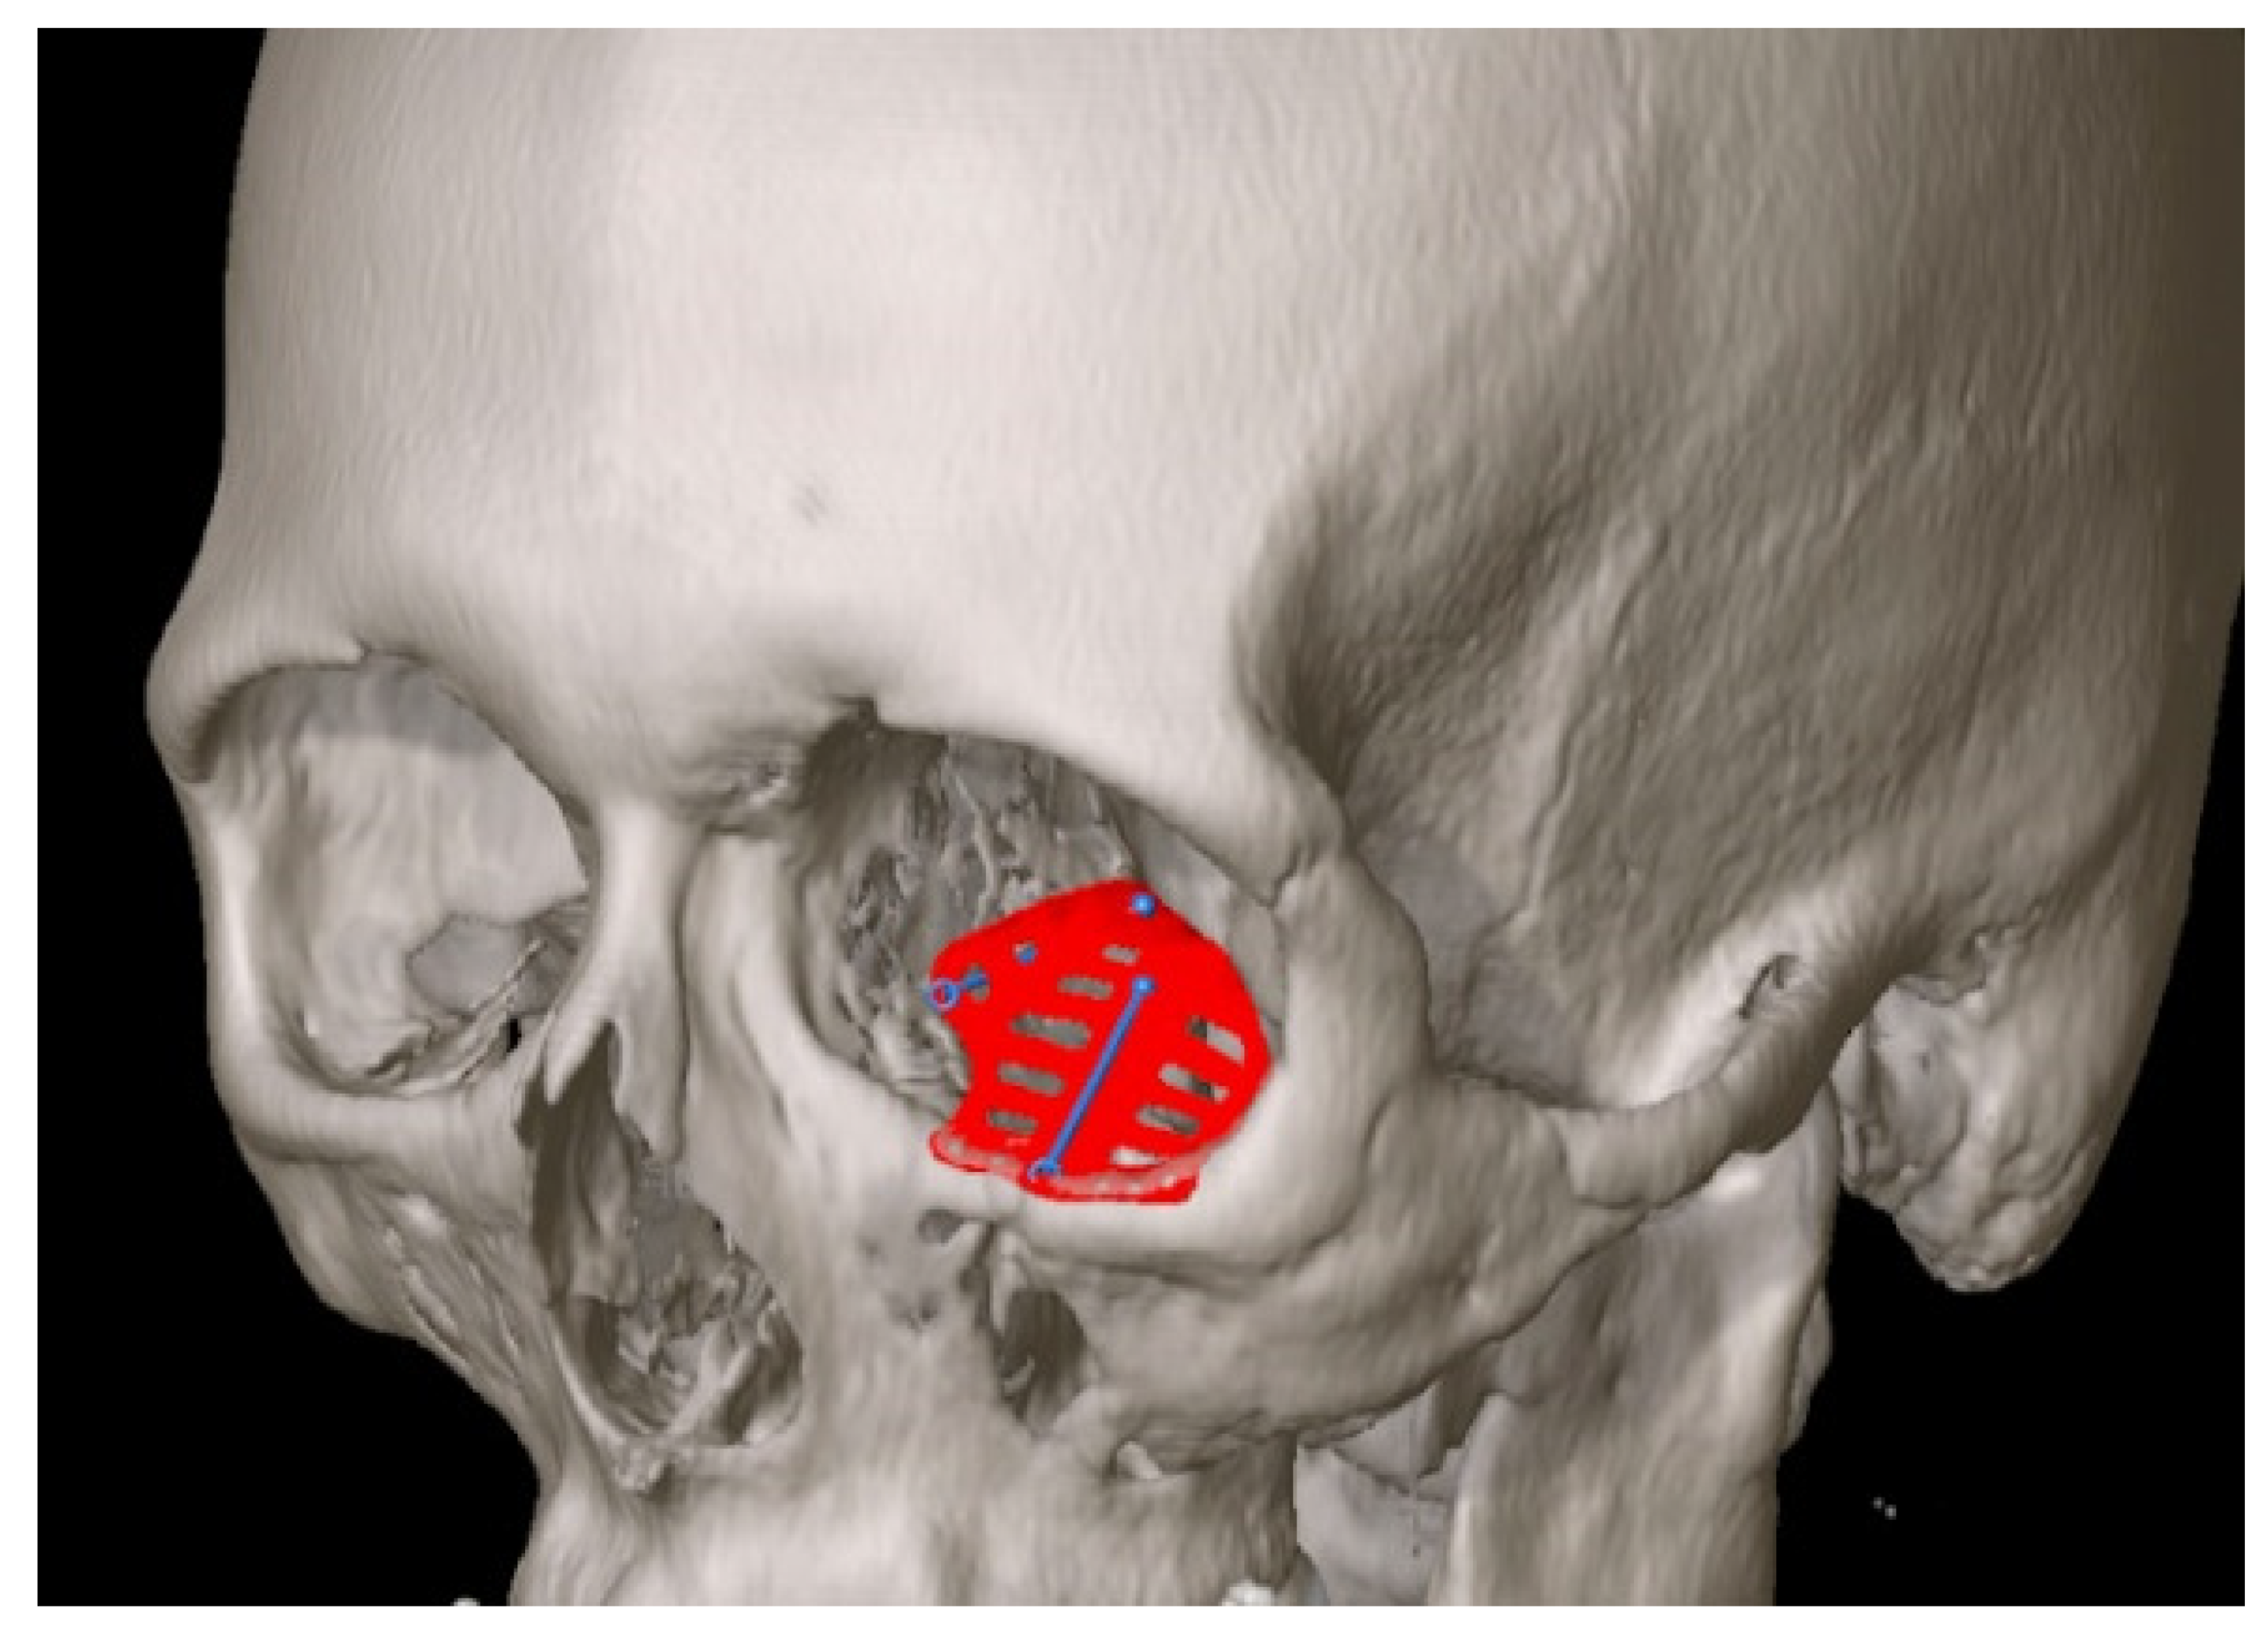

- Rana, M.; Gellrich, M.-M.; Gellrich, N.-C. Customised reconstruction of the orbital wall and engineering of selective laser melting (SLM) core implants. Br. J. Oral Maxillofac. Surg. 2015, 53, 208–209. [Google Scholar] [CrossRef]

- Rana, M.; Chui, C.H.K.; Wagner, M.; Zimmerer, R.; Rana, M.; Gellrich, N.-C. Increasing the accuracy of orbital reconstruction with selective laser-melted patient-specific implants combined with intraoperative navigation. J. Oral Maxillofac. Surg. Off. J. Am. Assoc. Oral Maxillofac. Surg. 2015, 73, 1113–1118. [Google Scholar] [CrossRef] [Green Version]